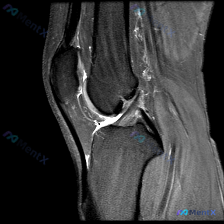

今天看到这个挺有讨论价值的读片问题,整理了完整信息和分析思路分享给大家。 病例/影像基本信息 这是一张膝关节轴位T1加权MRI图像,临床提出的问题是评估是否存在软骨异常。 我们先看这份影像的客观观察结果: 1. 整体解剖结构:髌骨、股骨远端滑车轮廓清晰,皮质骨光滑,无骨质破坏或骨皮质中断,骨髓信号大...

今天碰到一个很典型的临床判断和影像结果矛盾的情况,整理一下完整分析思路跟大家交流一下。 病例核心信息 这是一张膝关节MRI的轴位T1加权像,信息整理如下: - 骨骼结构:髌骨、股骨远端滑车区骨皮质连续,骨髓信号均匀,未见骨破坏或异常信号,髌骨关节软骨面轮廓正常 - 髌股关节:关节间隙可见,软骨表面清...

最近遇到一个有意思的读片病例:临床怀疑髌股关节软骨异常,但给出的单张T1加权轴位MRI却没看到明确病灶,整理一下整个分析思路分享给大家。 一、病例影像基础信息 这是一份膝关节MRI检查的T1加权轴位(横断面)图像,扫描层面位于髌股关节水平,先整理一下基础读片结果: 1. 解剖结构确认:前方为髌骨,后...